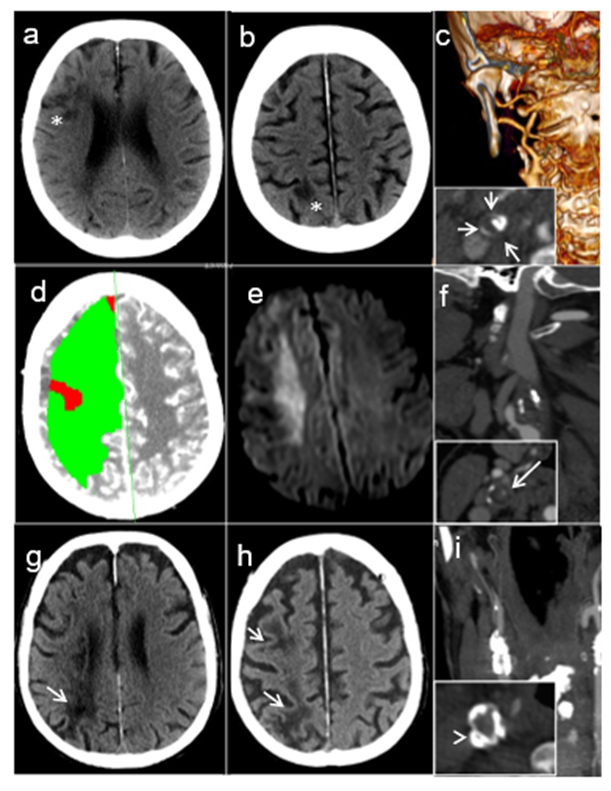

Patient 1: A 87-year-old female patient with incomplete resection of an undifferentiated squamous-cell carcinoma of the right tonsil (pT2 cN0 cM0, R1) was hospitalized for postoperative RT. RT planning included a total dose of 66 Gy in 2 Gy/fraction over 33 sessions delivered on the right tonsil, the adjacent lymphatics as well as the vascular axis and the right velum. Two days after the 11th fraction, the patient developed acute left hemiparesis, hemianopia and hemineglect. Brain computer tomography (CT) showed a right middle cerebral artery (MCA) stroke partially in borderzone territories (Figure 1A-B). Computed tomography angiography (CTA) showed right internal carotid artery (ICA) occlusion in its extracranial tract, displaying a “ring sign” characteristic of acute carotid occlusion [4] (Figure 1C). The patient died of unknown cause after 7 months at home.

Figure 1: Brain imaging of the three patients: A-C: Patient #1: Plain CT with borderzone infarcts in the anterior (A) and posterior (B) carotid territories (white asterisks). C) Angio-CT with ICA occlusion at its origin (carotid ring sign, short white arrows). D-F: Patient #2. D) Acute perfusion CT with global hypoperfusion of the right carotid territory. B): diffusion-weighted MRI at day 10 showing restriction of diffusion consistent with a right borderzone infarction. C) Angio-CT with ICA occlusion at its origin (carotid ring sign, long white arrow). G-I: Patient #3. G ) Plain CT with borderzone infarcts in the deep (G) and superficial (H) territories (white arrows). I) Angio-CT with right ICA occlusion at its origin (annular calcified plaque in the common carotid artery, white arrowhead).

Patient 2: A 57-year-old female smoker presented recurrent, transient episodes of left extremity shaking and left hemiparesis that were not investigated. Two weeks later after one of these episodes, she presented signs of superior vena cava syndrome. Oncological work-up showed a newly diagnosed small-cell lung carcinoma with bone and liver metastases. Brain MRI displayed a right cortical lesion initially interpreted as a metastasis. She started levetiracetam for presumed focal seizures. She underwent three cycles of palliative chemotherapy with cisplatin and etoposide. Nine days after the last administration, she received RT on cervical metastasis to prevent spine instability. A total dose of 20 Gy in 4 Gy/fraction was planned, but one hour after the first fraction, the patient presented a transient left leg paresis, followed five hours later by progressive left hemiparesis. Her palliative RT was completed. Brain CT showed an acute right MCA borderzone stroke (Figure 1D) confirmed ten days later by MRI (Figure 1E). Acute CTA showed right ICA with a ring sign, suggesting occlusion (Figure 1F). Retrospectively, the limb shaking, and right cortical lesions were interpreted as athero-embolic ischemic events from a preexisting right carotid stenosis. The patient died 3 months after stroke due to community-acquired pneumonia complicated by acute respiratory failure and septic shock.

Patient 3: A 68-year-old male active smoker with a history of arterial hypertension, diabetes, chronic alcohol abuse, was diagnosed with a left aryepiglottic keratinizing squamous cell carcinoma (cT3 cN1 cM0) after a routine CT-scan performed as part of liver cirrhosis follow-up. Brain CT showed a chronic minor right posterior borderzone stroke and further investigations with CTA displayed a 90% calcified asymptomatic stenosis at the origin of the right internal carotid. He received RT with a total dose of 69.36 Gy in 33 fractions of 2.12Gy on the primary tumor and internal jugular lymph node, as well as 52.8Gy in 33 fractions of 1.6 Gy on the cervical lymph node drainage areas bilaterally over 6 weeks. He received immunotherapy with cetuximab during the same period. Ten days after the last RT session and 16 days after the last immunotherapy administration, he presented with progressive left hemiparesis and hemineglect. CT and CTA demonstrated a subacute right borderzone MCA stroke and an internal carotid occlusion (Figure 1 G-H). ECG showed new-onset atrial fibrillation. 72 hours upon admission, the patient deceased due to aspiration pneumonia with sudden cardiordiorespiratory arrest. Autopsy demonstrated a right carotid artery thrombus (Figure 2A) and a left carotid artery atheromatous plaque with no signs of inflammation in the carotid walls (Figure 2B).